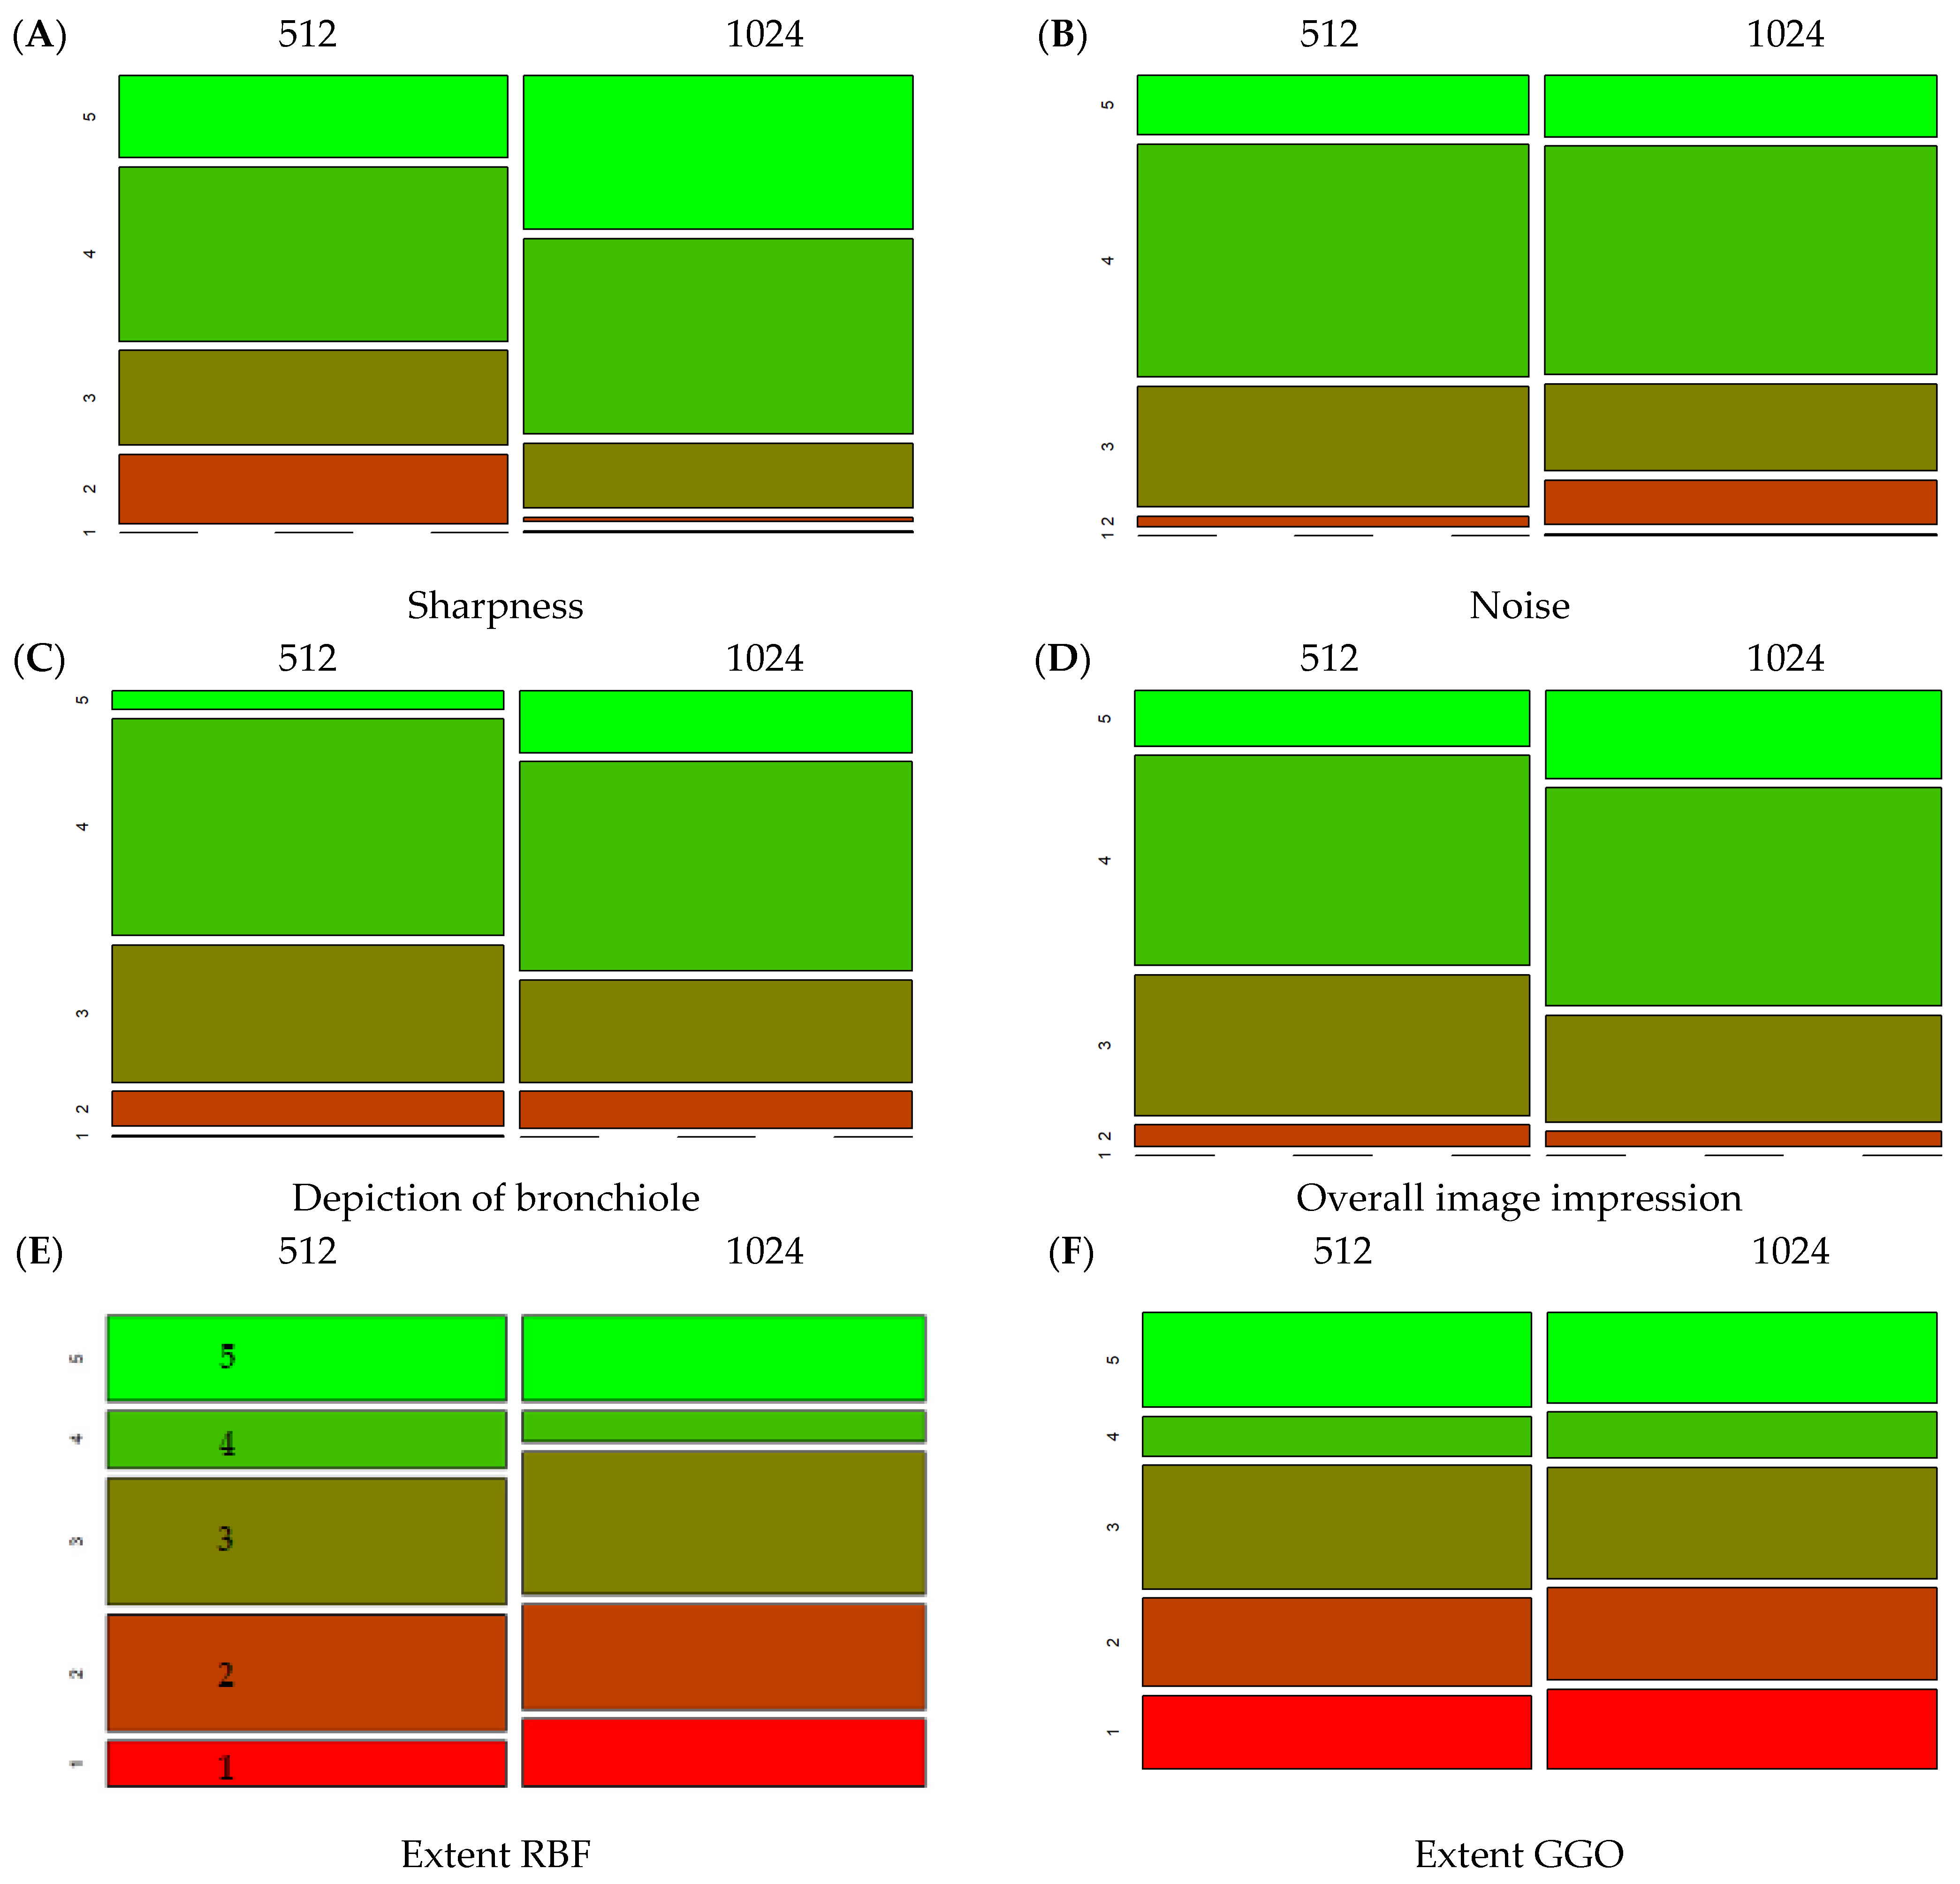

3.3. Comparison of Different Matrices

| 512 | 1024 | p (Wilcox.) | |||

|---|---|---|---|---|---|

| Mean | Sd | Mean | Sd | ||

| Sharpness | 3.64 | 0.98 | 4.18 | 0.76 | <0.01 |

| Noise | 3.81 | 0.70 | 3.72 | 0.86 | 0.09 |

| Depiction of bronchiole | 3.53 | 0.74 | 3.72 | 0.83 | <0.01 |

| Overall image impression | 3.70 | 0.76 | 3.89 | 0.77 | <0.01 |

| Extent RBF | 2.99 | 1.38 | 2.94 | 1.40 | 0.49 |

| Extent GGO | 3.05 | 1.27 | 2.91 | 1.31 | 0.04 |

| Total | 24.08 | 4.09 | 24.71 | 4.46 | <0.01 |